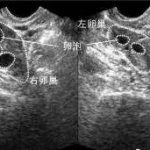

IVF-ET技术治疗成功率一般用临床妊娠率进行判定,即临床妊娠周期占胚胎移植周期的比例,而临床妊娠是指胚胎移植后28~30天阴道超声观察到宫腔内妊娠囊。不同的IVF中心成功率有差异,多数中心每移植周期的成功率可达30%~50%,部分中心报道每移植周期的成功率为60%~70%,临床治疗成功率受多种因素的影响,如患者的选择、临床治疗方法、实验室技术等。